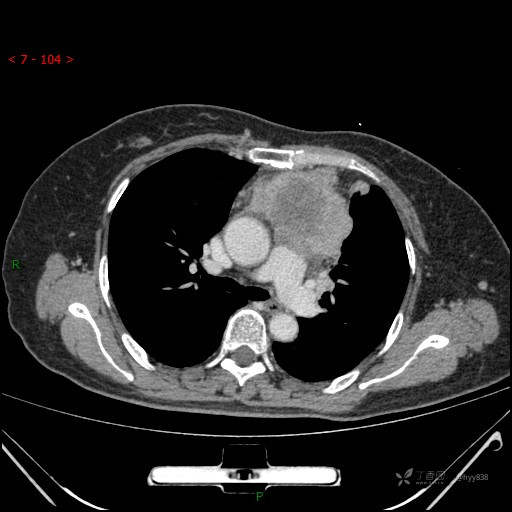

辅助检查:CT

动脉期

静脉期